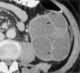

Multilocular cystic renal tumor

Multilocular cystic nephroma